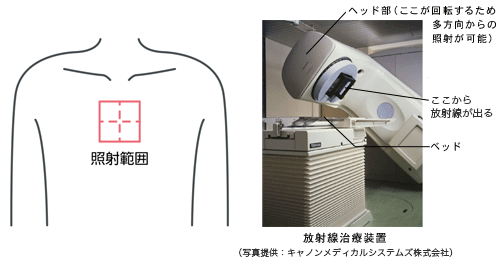

肺がんに対する放射線治療後、間質性肺炎を発症することがあり、このような肺炎を放射線肺炎(放射線肺臓炎)といいます。放射線肺炎は、放射線によって肺の組織が壊れることによって発症し、多くの場合、照射後1〜6ヵ月以内に起こります。